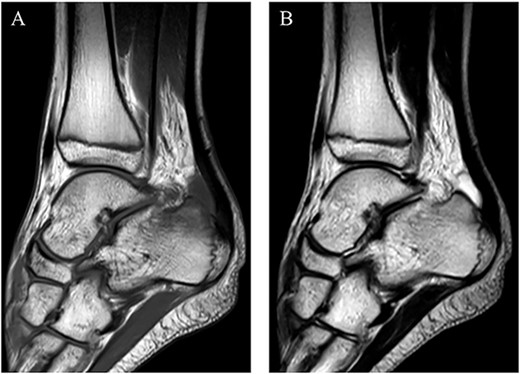

Postoperatively, intravenous antibiotic therapy using cefazolin (6000 mg per day) was continued for 10 days until laboratory results was within normal. A non-weightbearing splint was applied for postoperative 1 week. Active range of motion exercises and partial-weightbearing were started at 1 week postoperatively, and full-weightbearing at 2 weeks postoperatively. At 4 weeks after the surgery, he could return to the original sport at preinjury level without symptoms and complications. In addition, MRI revealed no abnormal signs at 1 year postoperatively (Fig. 5). Two years after the surgery, he remained a competitive soccer player without symptoms and recurrence.

MRI revealed no abnormal signs on short TI inversion recovery images at 1 year postoperatively.